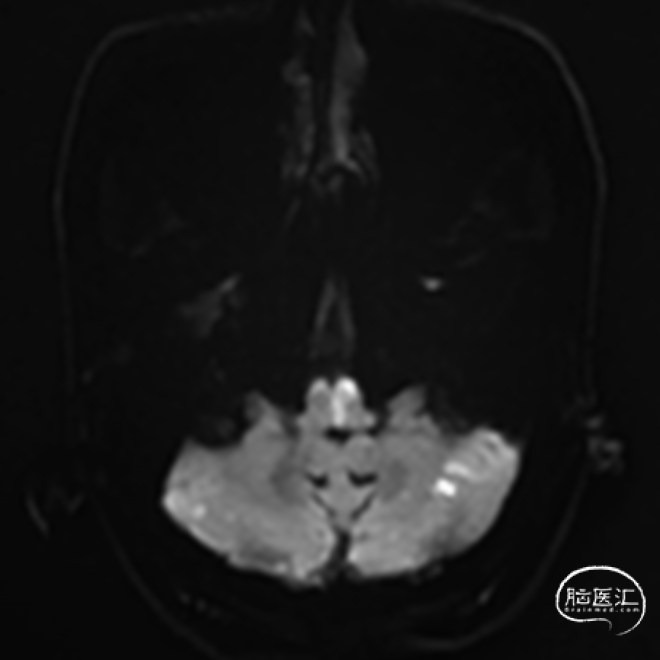

➢2024.07.08 外院颅脑MR提示:

双侧小脑及桥脑多发急性脑梗死,基底动脉闭塞?大脑后动脉狭窄。

➢2024.07.10 MR:

核磁共振提示发病机制穿支事件+低灌注

高分辨核磁提示左侧椎动脉V4段不稳定斑块